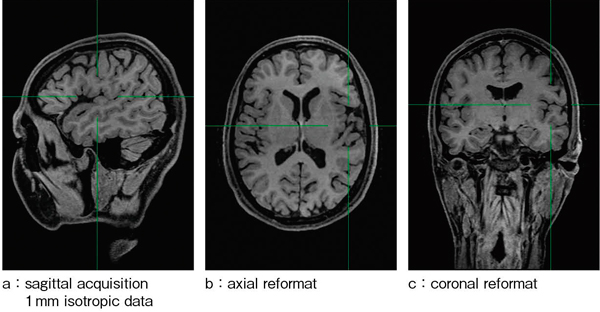

1mm isotropic dataは,readout,位相,スライス方向にzero fill interpolationより補間され,見かけ上0.5mmの空間分解能を持っている(図1)。そのため,拡大処理をした下垂体部の描出も良好で(図2),下垂体後葉がしっかり高信号となり,コントラストも良好である(図2↑)。図2 bの冠状断像では,大脳基底核だけでなく,視交叉周囲の脳脊髄液と中大脳動脈のflow voidのコントラストもしっかりと保たれている。

図1 isoFSE T1強調画像